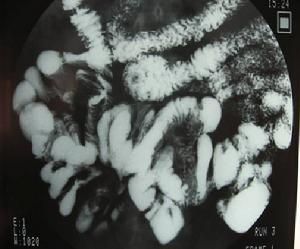

1.3 X線鋇餐檢查:可見小腸受壓、緊縮、小腸整塊移動或迴腸末段狹窄等徵象,鋇劑通過小腸的時間明顯延長,短縮的腸系膜及纖維內壁的粘連可使小腸出現類似結腸袋樣的徵象。

2.3 X線可發現全部或部分小腸聚攏於某一部分,位置固定。